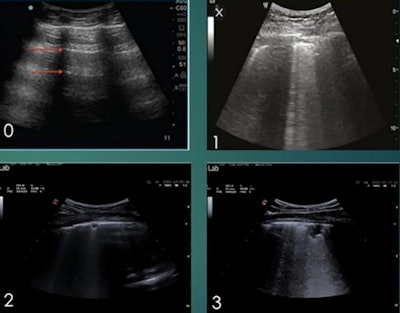

During the webinar, Sabatini also shared research he presented on 10 December at the ASA meeting demonstrating the benefit of lung ultrasound scans as a diagnostic tool for COVID-19. He and his colleagues found that the total lung ultrasound score on admission to the hospital was associated with higher odds of a patient's condition worsening.

The study was based on lung ultrasound scans of 52 patients with confirmed COVID-19 cases who were admitted to the Pavia hospital between 15 March and 29 April. Sabatini and colleagues performed lung ultrasound scans on the patients, then used those scans to calculate lung ultrasound scores.

Patients with worse lung ultrasound scores at admission were more likely to experience a continued worsening of their clinical condition. Patients with the worst score in three different lung sections had a six times greater chance of experiencing worsening outcomes.

Conversely, ultrasound findings improved as patients recovered. The proportion of patients with severe disease decreased significantly among patients with a second ultrasound scan after 10 days in the hospital -- a finding that "underlies the importance of lung ultrasound for patient monitoring," Sabatini said.

The findings add to prior research demonstrating that lung ultrasound scans and associated lung ultrasound scores can help clinicians quickly determine the severity of COVID-19 infection. Sabatini added that this information can also be used to inform patient management and medication decisions.